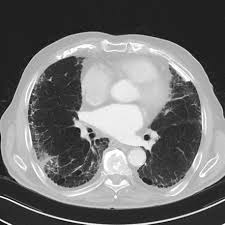

Asbestosis Pulmonary Disorders Msd Manual Professional Edition

Asbestosis Pulmonary Disorders Msd Manual Professional Edition from www.msdmanuals.com